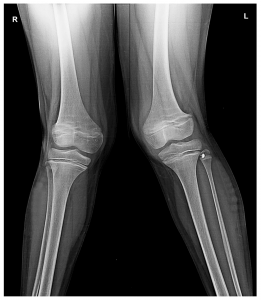

A physical assessment of the legs and gait will be performed. The diagnosis can be confirmed with a standing-alignment X-ray or EOS pictures. These are radiographic images of the leg from the hip to the ankle that assist the clinician in determining the exact position and mechanical axis of the deformity. A doctor diagnoses the cause of genu valgum in older children and adults.

Do You Know About Knock Knees?

It is a condition in which a person’s knees bend inward and “knock” against one another, even when their ankles are separated. Excessive force is applied to the outer side of the knee, which can result in pain and damage over time.

Knock knee is usually bilateral, affecting both legs, but it can also affect only one knee in some circumstance.